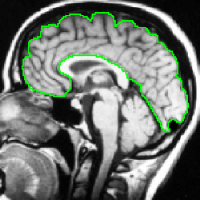

Finally, the “weighted cut” is recovered in (26), and the “smoothness term” is compatible with large variations of at the boundary of objects because of a large denominator () in the contour area. An illustration of optimal and on an image is shown on Fig. 2.

We begin by comparing the CCMF segmentation result with the classical max-flow algorithm (graph cuts). Figure 3 shows the segmentation of a brain, in which the contours obtained by graph cuts are noticeably blocky in the areas of weak gradient, while the contours obtained by both AT-CMF and CCMF are smooth.

Figure 2 displays the performance results for these algorithms. The Dice coefficient is a similarity measure between sets (segmentation and ground truth), ranging from 0 to 1.0 for no match and a perfect match respectively. All the tested algorithms show very good results, with a Dice coefficient of 0.95–0.97 for the well positioned seeds, and 0.89–0.92 for the second set of seeds, further away from the objects. The CCMF and AT-CMF results are really close, and the mean is better than the GC and the CP-TV results.